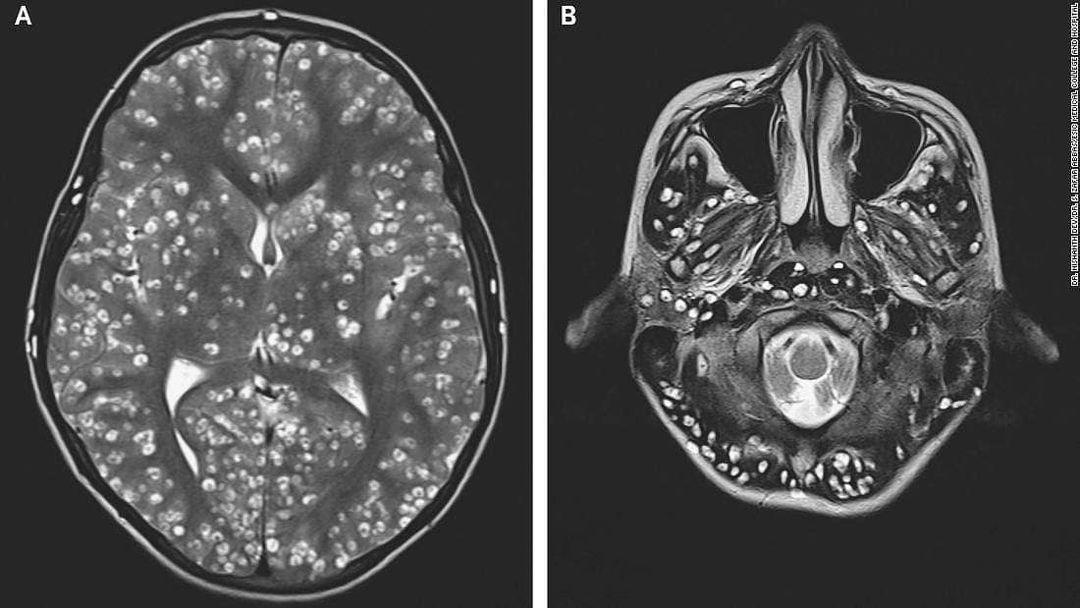

An 18-year-old who complained of seizures in the emergency room of an Indian hospital turned out to have parasites in his brain, according to a case study published Thursday in the New England Journal of Medicine. Drs. Nishanth Dev and S. Zafar Abbas of the ESIC Medical College and Hospital in Faridabad reported that the patient, who appeared in the ER with swelling over his right eye, was having tonic-clonic seizures. Formerly known as "grand mal" seizures, these neural disturbances cause stiffened muscles and a loss of consciousness. His parents said that their son had felt pain in his right groin for a week. A physical exam revealed that he had tenderness in the right testis and was feeling confused. To learn more about his condition, the medical staff performed an MRI exam and saw damage caused by cysts in his cerebral cortex (the outer mantle of brain tissue) as well as the brain stem, including the cerebellum, which sits at the back of the head above the spinal cord. Diagnosis: neurocysticercosis, a parasitic disease of the brain caused when someone swallows tapeworm eggs that have passed in the feces of someone who has an intestinal tapeworm. The larvae crawl out of the eggs and into muscle and brain tissues, where they form cysts. The doctors also discovered cysts in the patient's right eye and right testis. Because of the number and location of the cysts, his doctors decided against treating the young man with antiparasitic medications. These can worsen brain bleeding and inflammation while leading to loss of vision. Instead, the patient was given an anti-inflammatory drug, dexamethasone, plus antiepileptic medications. Two weeks after his arrival in the ER, the patient died, Dev and Abbas report.